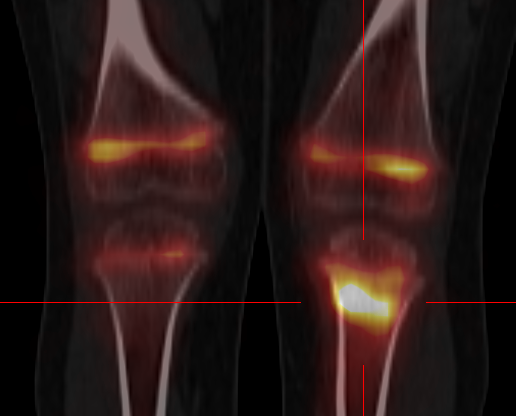

-Suspicion d'ostéonécrose (têtes fémorales, condyles fémoraux, plateaux tibiaux, pied, tête humérale, semi-lunaire...)

-Arthrose (rachidienne, coxo-fémorale, gonarthrose, rhizarthrose, interphalangienne, sterno-claviculaire, gléno-humérale...)